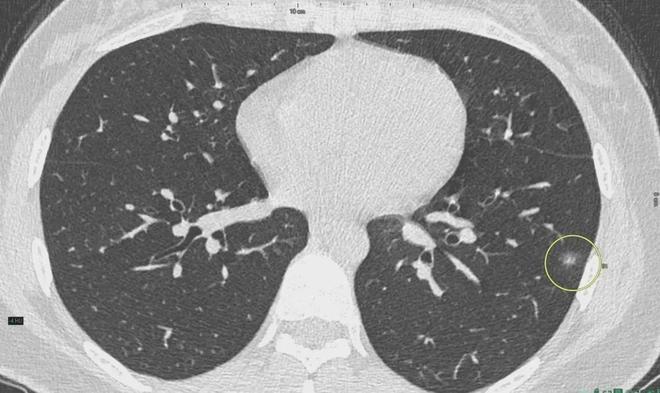

肺結(jié)節(jié)是一種常見的肺部疾病,其發(fā)病率逐年上升,雖然肺結(jié)節(jié)多數(shù)情況下是良性的,但也有可能惡化為肺癌,了解肺結(jié)節(jié)的形成原因?qū)τ陬A(yù)防和治療具有重要意義,本文將為您詳細解析肺結(jié)節(jié)的形成機制。

6、定期體檢:定期進行肺部檢查,及時發(fā)現(xiàn)并治療肺結(jié)節(jié)。